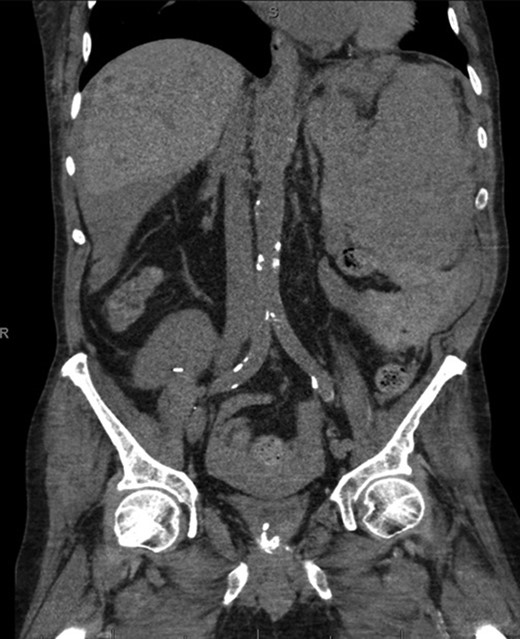

A 68-year-old male with history of living donor renal transplant presented to the ED with acute onset of profound weakness, fatigue, left upper quadrant abdominal pain, hypotension and lactic acidosis. On exam, he exhibited mild left upper quadrant and epigastric tenderness without evidence of peritonitis. CT imaging demonstrated splenomegaly with a large splenic hematoma measuring 15.7 × 9.2 × 12 cm and associated hemoperitoneum (Figs 1–3). In addition, innumerable osseous lytic lesions were identified. Given these findings, emergent surgical consultation was obtained and his coagulopathy reversed. He remained hypotensive despite resuscitation, thus was taken for laparotomy. Upon abdominal entry, a large amount of old clot was evacuated. The abdomen was packed in all quadrants in the standard fashion. Upon removal of the left upper quadrant packs, active hemorrhage began to well from the region of the spleen which was mobilized and removed via splenectomy. Upon gross inspection, the spleen was hyperemic and abnormally indurated, with an avulsion type injury extending several centimeters across the inferior pole. There was no evidence of pseudoaneurysm or other gross pathology. Given the patient was mildly hypothermic and coagulopathic with continued oozing from the retroperitoneum, the decision was made to pack the splenic fossa and place a temporary wound vac. The patient was transported to the ICU for resuscitation and brought back to the OR the next morning for re-exploration and closure. Despite hemodynamic stabilization, he underwent a prolonged hospitalization complicated by atrial fibrillation, renal allograft failure, VAP, and ultimately PEA arrest progressing to asystole. He died 6 weeks following splenectomy. The pathology from the spleen revealed splenomegaly with parenchyma that was replaced with amorphous and acellular eosinophilic material. Histologic staining (Thioflavin-T) was positive for amyloidosis, AL-type. Oncology was consulted based on these findings with concern for lymphoproliferative disorder given osseous findings on CT, splenic pathology, and history of immunosuppression. Bone marrow biopsy was subsequently obtained which showed more than 50% atypical plasma cells/plasma blasts (CD138+; PAX5 negative; EBV (EBER) negative) and no amyloidosis, consistent with multiple myeloma. Urine showed Bence-Jones protein. Serum immunofixation studies were remarkable for a monoclonal IgG lambda gammopathy, consistent with the diagnosis of AL amyloidosis associated with systemic myeloma.

Coronal CT imaging demonstrating splenomegaly with splenic capsule rupture at the inferior pole with heterogeneous fluid in the paracolic gutters and perisplenic region suggestive of hemoperitoneum.